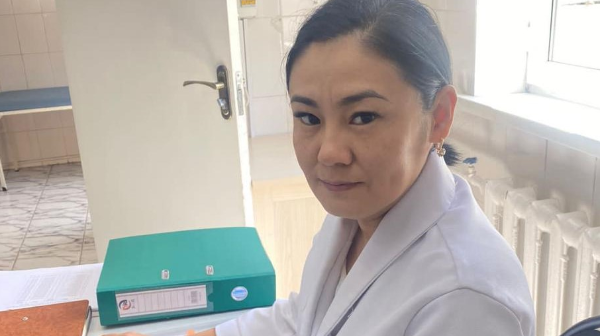

اۆتور: نۇرجامال ءالىش

اۆتور: نۇرجامال ءالىش